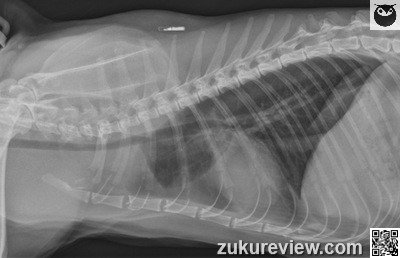

Question of the Day

Put your knowledge           to the test

Cat looking up